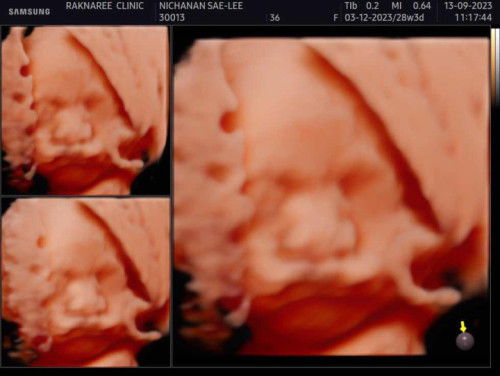

วันนี้แม่ไปอัลตราซาวด์4มิติ ลูกชายไม่ค่อยให้ความร่วมมือสักเท่าไหร่เลยค่ะ หลับตลอด เอามือปิดหน้า แถมทำหน้าตาบึ้งตึงใส่หมอ ขำหน้าลูกตัวเอง😂😂 น้ำหนักน้อง 1160g 28+3 แม่ๆว่าน้ำหนักน้องตามเกณฑ์ไหมคะ ? ลูกแม่ๆน้ำหนักเท่าไหร่กันบ้างคะ?หมอแจ้งรายละเอียดดีมาก ตั้งแต่หัวจรดเท้า ทุกอย่างปกติมากก ได้ยินแบบนี้แม่ใจฟูสุดๆเรยย😁😁##ขอบคุณสำหรับคำตอบค่ะ